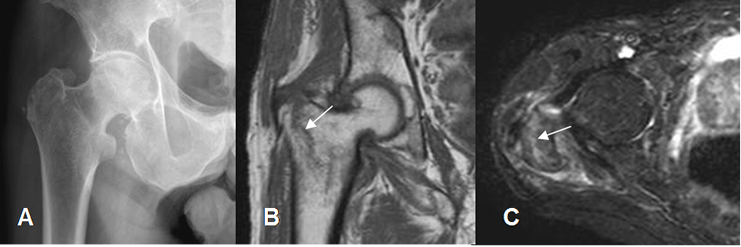

Fig 46. Fractura.

A: Rx AP sin alteraciones.

B: RM coronal en T1 y C: RM axial en STIR. Fractura no desplazada (Flechas), sobre el trocánter mayor.